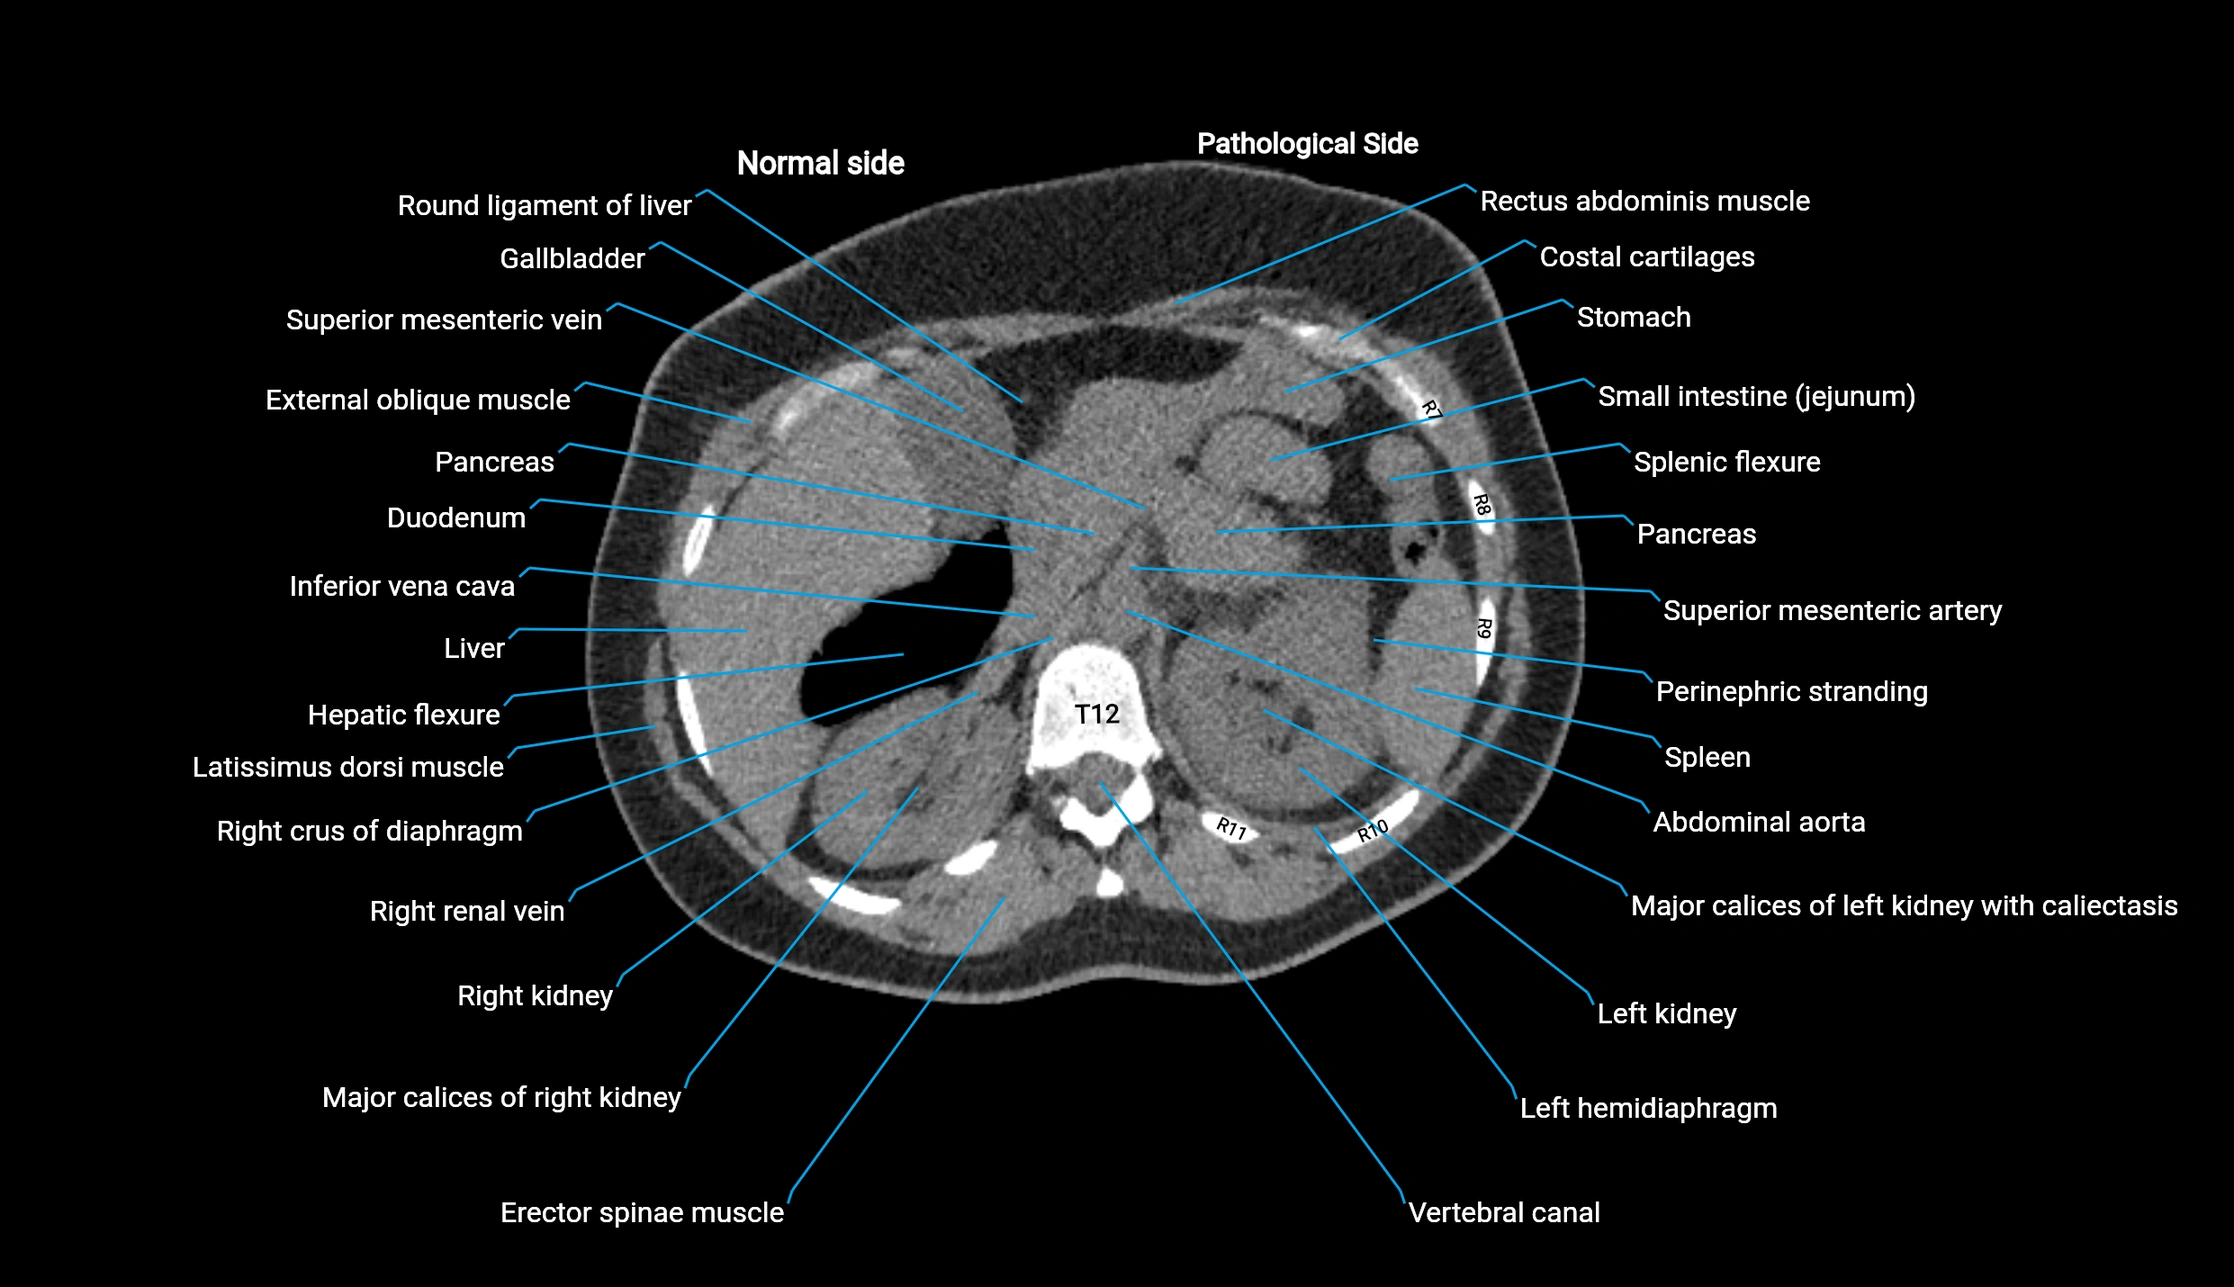

Post-Contrast CT (Contrast-Enhanced CT):

• Portal venous phase:

• Anterior right portal branch enhances intensely and homogeneously

• Clearly separates from posterior branch

• Branching pattern to segments V and VIII sharply defined

• Arterial phase:

• Slight enhancement but less conspicuous than in portal phase

• Coronal and sagittal reconstructions:

• Optimal visualization of segmental bifurcation

• Used for preoperative liver mapping

• CT liver segmentation:

• RAPV acts as the principal boundary landmark for dividing anterior vs. posterior right hepatic segments